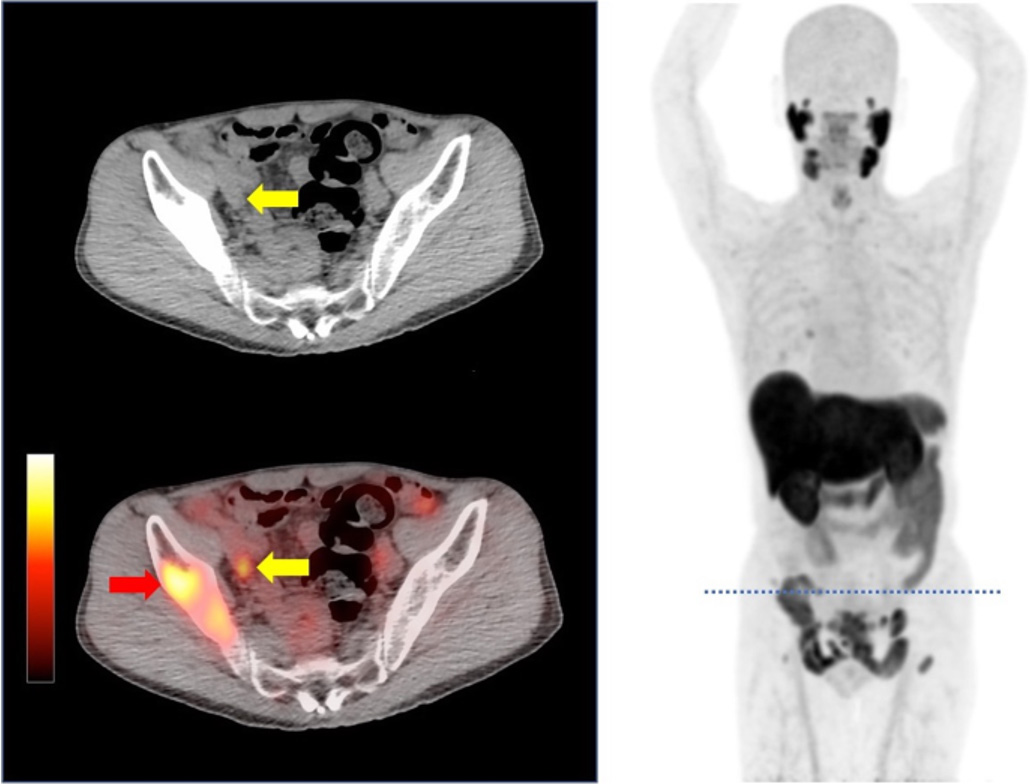

02. 18F‑PSMA

Targets PSMA to detect prostate cancer at staging and recurrence, delivering high‑contrast pelvic imaging.

04. 68Ga-PSMA

PSMA-targeted PET imaging agent for prostate cancer diagnosis, treatment response assessment, and recurrence detection.